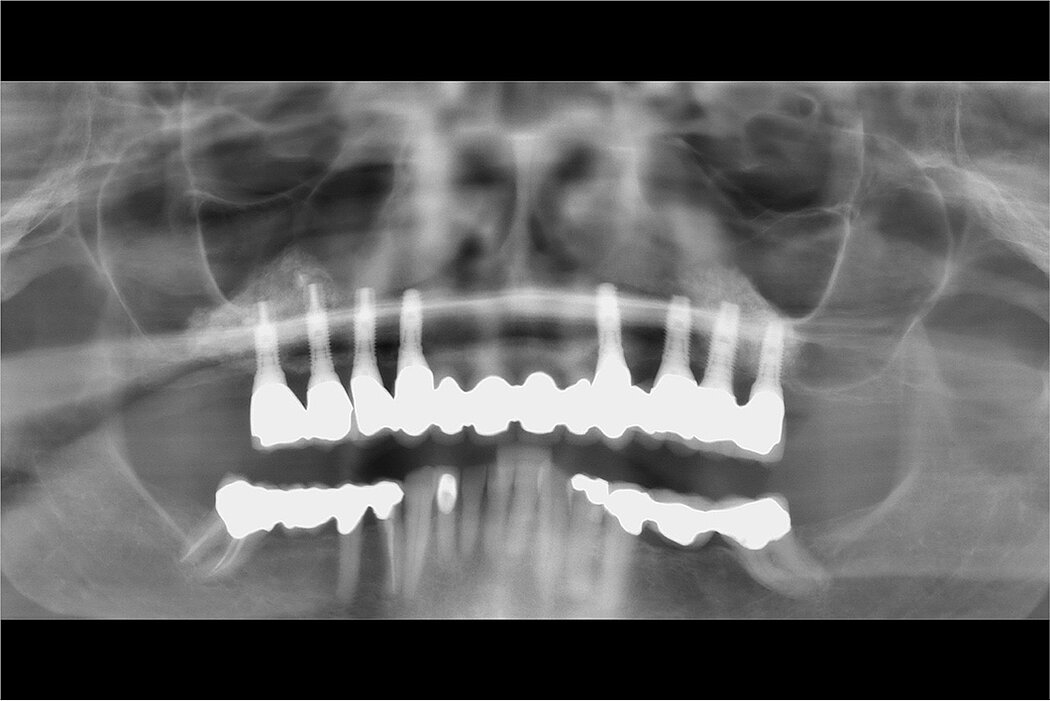

A 63-year-old female patient presents with hopeless maxillary teeth and a desire for a fixed reconstruction. A staged case was planned with the canines used as abutments for a fixed provisional while sinus augmentation and delayed implant placement were being accomplished. The case presented with 1-2mm of crestal bone in the molar sites. During sinus augmentation surgery the thin Schneiderian membrane on the right ridge was extensively torn. A collagen membrane repair procedure was performed and bilateral sinus augmentations were completed with Geistlich Bio-Oss® as the sole grafting material covering the lateral window with a Geistlich Bio-Gide® membrane. After an extended delay (financial) implants were placed in the grafted sinuses and a bone core harvested through the lateral window. The anterior teeth were extracted and the provisional was extended to the posterior implants. Implants were later placed in the canine sites and the final prosthesis was fabricated. The final follow-up is 13 years on from the sinus augmentation.

- Staged sinus floor elevation with 100% Geistlich Bio-Oss® and Geistlich Bio-Gide® when only 1–2mm crestal bone remains

- Fixed maxillary reconstruction on both sides

- Successful implant placement 1-year after sinus floor elevation

- Two-stage sinus floor elevation treatment

- Successful sinus floor elevation of severe pneumatization with Geistlich Bio-Oss® and Geistlich Bio-Gide® shows stable bony volume after 13-year follow-up

- Sinus augmentations performed with 100% Geistlich Bio-Oss® when only 1–2mm of crestal bone remains

- Achieving a successful result in theface of an extensive perforation

- Assuming some loss of the existing crestal bone due to biologic width formation, the molar implants have existed with Geistlich Bio-Oss® likely at the crest for close to 10 years

- Geistlich Bio-Oss® alone, covered with a Geistlich Bio-Gide® membrane can give successful results in compromised clinical situations. Histomorphometric Evaluation showed 31% vital bone with all implants successful by any guidelines.

- Having Geistlich Bio-Oss® exposed at the crest did not result in peri implantitis.